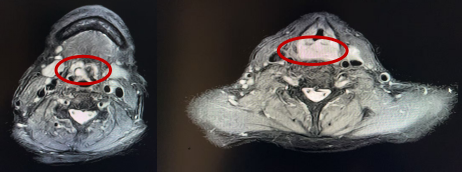

术前影像

患者男,62岁,因“喉部疼痛6年余,声音嘶哑半月”来院就诊。完善相关检查后,刘吉峰副主任医师发现,该患者病情复杂,肿瘤不仅在喉部广泛扩散,更侵袭至环后区及食道入口,严重威胁患者的呼吸与吞咽功能。入院后,刘吉峰副主任医师团队迅速组织了多学科MDT会诊,联合消化内科、胸外科、麻醉科、病理科、放射科等多个科室的专家共同开展病例讨论,为患者量身订制了精准的手术方案及后续治疗计划,为手术顺利实施提供了有力保障。